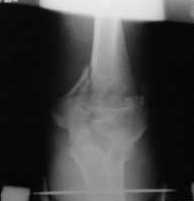

Подскажите пожалуйста, как можно в дальнейшем этому больному помочь. В марте первая

операция, пришлось оперировать на 16 сутки в виду инфицированных садин и анемии. Заживление

первичным натяжением, ранняя разработка после операции, а через 2 нед болевой синдром,и

постепенно движения в локтевом суставе ограничились до полного анкилоза. Повторно через 4

месяца вторая операция - артролиз, удаление оссификатов, удаление фиксаторов,

реостеосинтез этой же реконструкционной пластиной и винтом. Интраоперационно после

удаления оссификатов и фиксаторов обнаружил, что переломы не сросшиеся, поэтому пришлось

синтезировать заново. Зажила рана первично, объем движений в локтевом суставе сгибание 70,

разгибание160, ротационные движения востановились полностью, вроде бы успокоились.

Опять постепенно в течении 8 нед после повторной операции постепенно движения ограничились

до 80 - 110, на снимке оссификат. Снимки во вложении, буду рад Вашим советам. Спасибо!